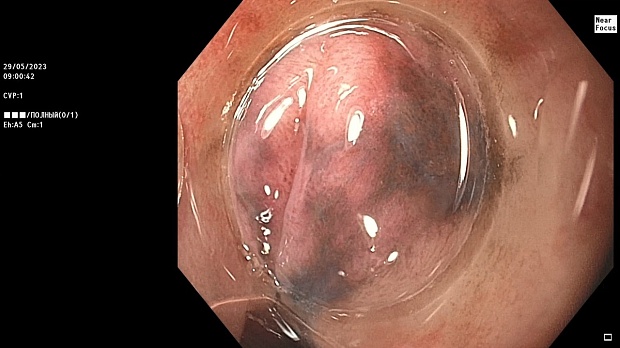

Иллюстрация №1: Эндофото. Сидероз нижней трети пищевода, осмотр в белом свете

Согласно полученным данным - в среднегрудном и нижнегрудном отделах пищевода определялась проксимальная граница плоских неправильной формы поверхностных рубцов суммарной протяженностью до 8,0 см. На этом фоне в зонах поверхностных рубцов по задней полуокружности визуализировались участки гиперпигментации в темный цвет (Рис. 1). При исследовании в режиме Dual Focus было отмечено наличие мелких (до 0,001 см) черно-коричневых включений, расположенных субэпителиально - в строме слизистой оболочки, сливания их в единый конгломерат не определялось (Рис. 2). При эндосонографии с применением минидатчика с частотой сканирования 20МГц выявлено, что все слои стенки четко дифференцируются, не утолщены, в слизистой оболочки визуализированы мелких гиперэхогенные включения с эхотенями (Рис. 3).

Протокол ЭГДС

В пищеводе в шейном его отделе на уровне 16 см от резцов циркулярно визуализированы единичные синюшные флебоэктазии размерами до 0.5 см. Дистальнее пищевод визуально не изменен до уровня 28 см от резцов, где определяется проксимальная граница плоских неправильной формы поверхностных рубцов, распространяющихся до уровня 36 см от резцов. На этом фоне в зонах поверхностных рубцов по задней полуокружности визуализированы участки гиперпигментации в черно-коричнеый цвет. При осмотре в режиме Near Focus с увеличением - между зон пигментации определяются расширенные капилляры типа II по Inoue-классификации. При биопсии отмечена десквамация плоского эпителия, визуализированы мелкие черно-коричневые включения в строме слизистой оболочки, размеры их до 0,001 см, сливания их в единый конгломерат не отмечается. При эндосонографии с датчиком 20Мгц в исследуемой зоне в слизистой оболочке определяются гиперэхогенные включения, в то время как в подслизистом слое - зоны со сниженной эхогенностью. При биопсии отмечается уплотнение ткани, однако истинной фрагментации не определяется. Уровень Z-линии совпадает с уровнем анатомического кардиоэзофагеального перехода. Розетка кардии эластичная, смыкается не полностью, расположена на уровне пищеводного отверстия диафрагмы.